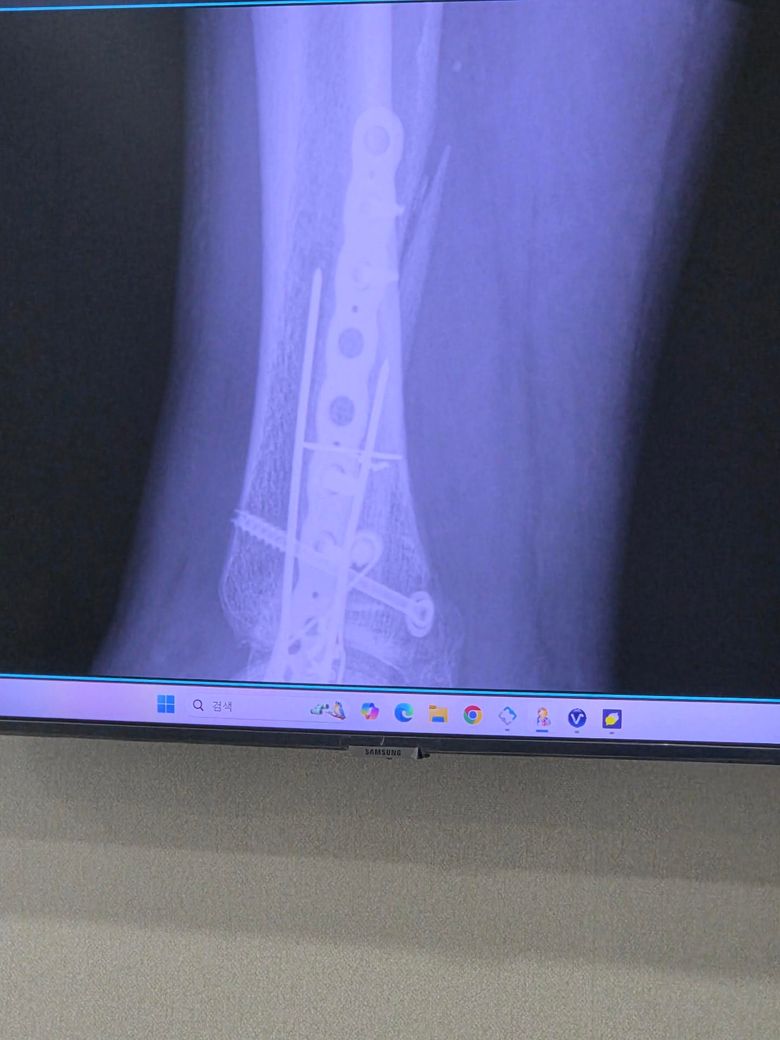

발목 삼과골절 12주차 질문입니다.

발목 삼과골절 수술후 12주차 입니다만 발 디딜때 통증으로 아직 보조기와 목발 2개(아주 가끔 1개 사용)사용중 입니다.

• 2번 째 사진